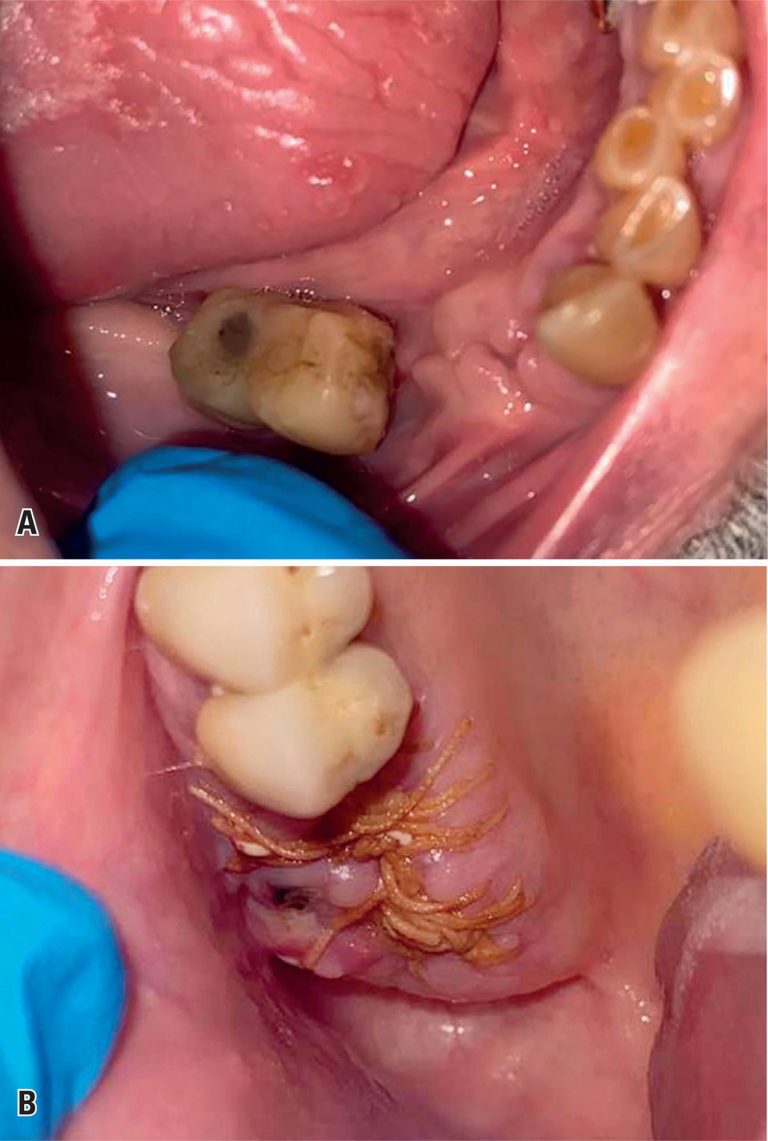

Severe bleeding diathesis after dental extractions: a complex case of coagulation disturbances in a patient with multiple myeloma

This case report describes a male patient diagnosed with multiple myeloma who experienced significant bleeding from both the maxillary and mandibular dental sockets following dental extraction, lasting several days. Laboratory tests revealed prolonged prothrombin time and thrombin time, accompanied by reduced factor VII levels. Initial management with intravenous vitamin K and fresh frozen plasma failed to achieve hemostasis. Despite the risk of thrombosis, low-dose tranexamic acid was initiated, resulting in effective hemorrhage control and improved healing of the alveolar sockets. This case illustrates the complex hemostatic imbalance between pro- and anticoagulant factors in a patient with multiple myeloma. It also underscores the diagnostic and therapeutic challenges associated with managing bleeding in patients with a high risk of thrombosis.